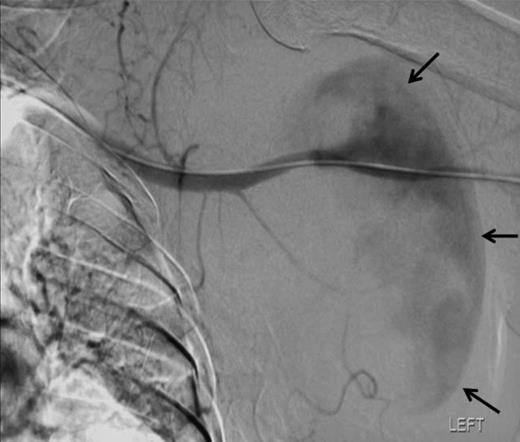

To attempt endovascular repair, an operative approach to the brachial artery preceded retrograde insertion of a 6cm long, 8mm thick Fluency nitinol self-expanding PTFE covered stent (Bard). This excluded the lesion successfully (figures 4 and 5). The haematoma was decompressed. Aspirin 75mg and clopidogrel 75mg were initiated for stent protection. The patient suffered a postoperative axillary wound infection which was treated successfully with antibiotics. There had been no recovery of neurological function in the arm. Neurophysiological studies revealed a proximal axonotmesis with a poor prognosis.

Angiographic localisation of the lesion in the third part of the axillary artery. Please note extravasation of contrast into the sac (arrows)

The lesion was repaired by an endovascular retrograde approach whereby the neck of the lesion was located just distal to the origin of the subscapular artery and the cavity excluded successfully by the insertion of self-expanding Fluency nitinol PTFE-covered stent (Bard). Such a method was favoured here because the condition of the arm rendered open approaches hazardous. There are several reports of the treatment of such lesions by stent graft, including those of Xenos (10), whilst open repair also offers a simultaneous opportunity to explore for and deal with associated injuries.